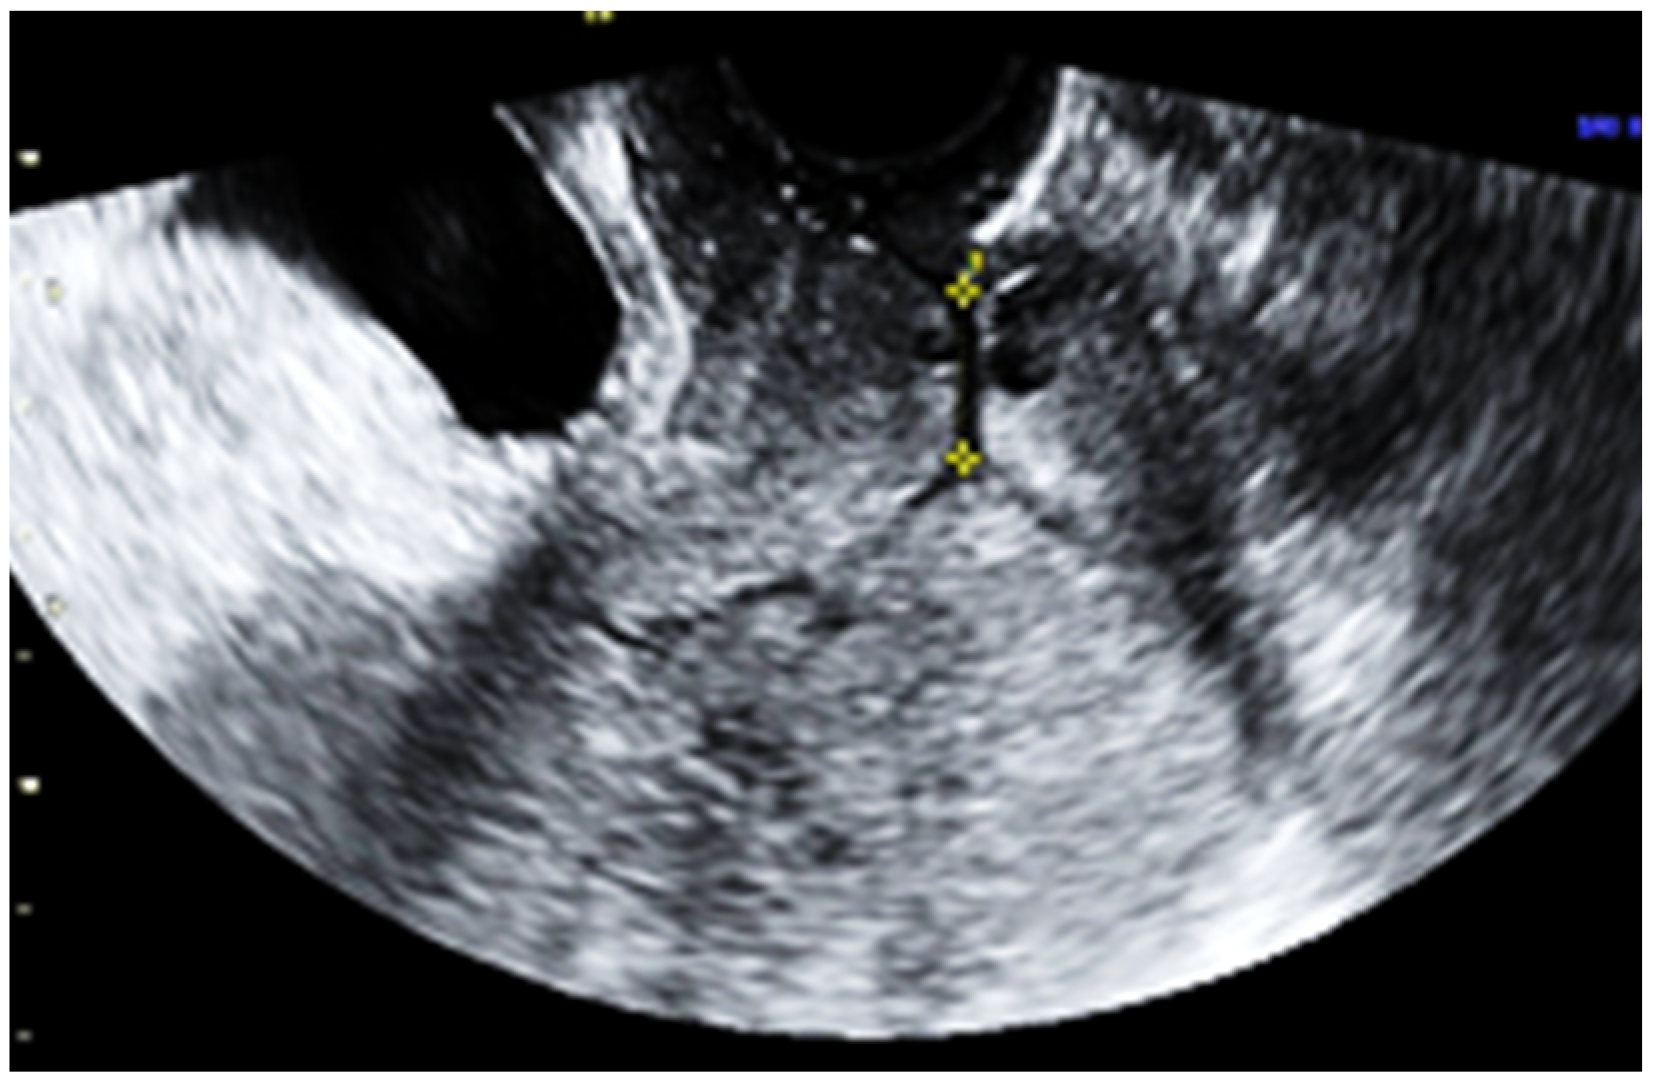

Subsequent ultrasound examination revealed a uterus with a homogeneous structure measuring 67/52/61 mm (Figure 1). However, in the lower portion of the uterine cavity and the upper part of the cervical canal, there was a non-homogeneous hyperechogenic mass measuring 72/30/75 mm (Figure 2). The mass exhibited numerous vessels (Figure 3), while the lower portion of the cervix appeared normal with a length of approximately 13 mm (Figure 4).

Figure 3.

The mass with increased vascularity.